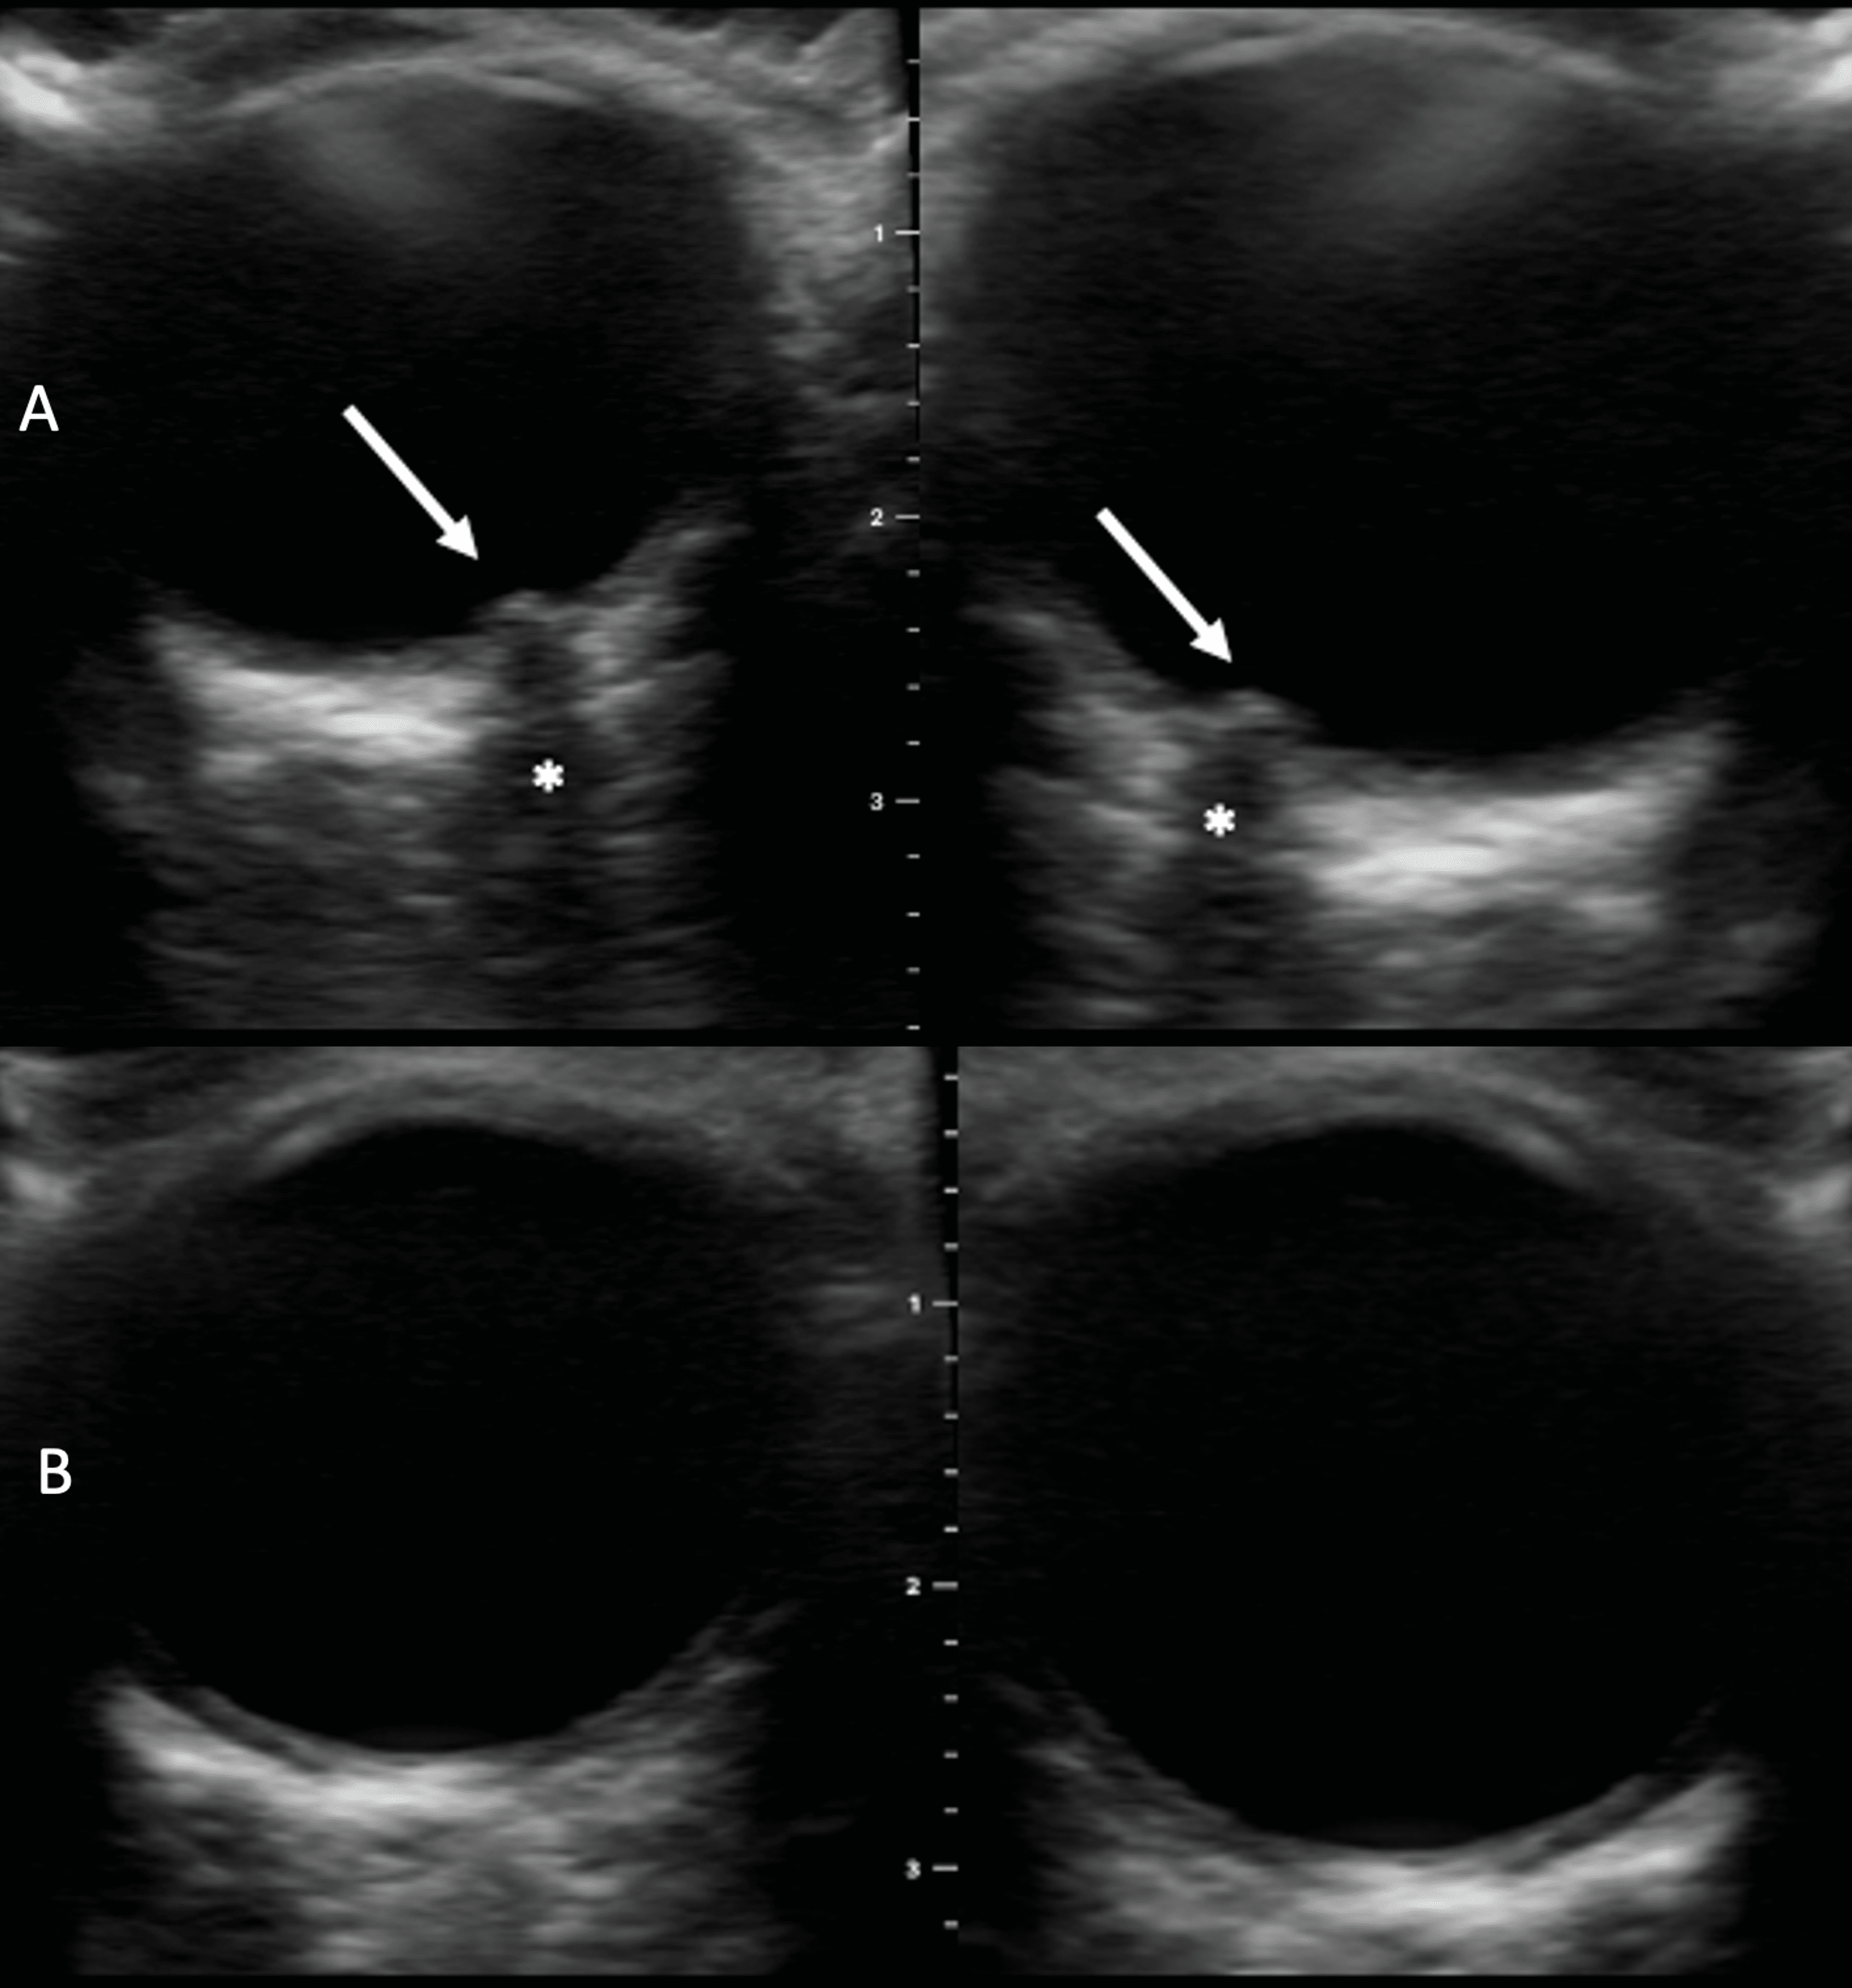

Ocular POCUS images demonstrating measurements of ONSD and ODE. A The Optic Disc Elevation The optic disc is an elevation on the medial aspect of the retina where the sensory fibers and retinal. Download the cheat sheet with clinical photographs and disease breakdowns. Papilledema refers to the swelling of both optic discs in your eyes due to increased intracranial pressure. Optic disc edema results from compression, infection, infiltration, inflammation, demyelinating disease or reduced perfusion. Optic Disc Elevation.

Bscan ultrasonography of both eyes showed optic disc elevation with Optic Disc Elevation Optic disc edema results from compression, infection, infiltration, inflammation, demyelinating disease or reduced perfusion to. The optic disc is an elevation on the medial aspect of the retina where the sensory fibers and retinal. Download the cheat sheet with clinical photographs and disease breakdowns. Learn how optometrists can identify, diagnose, and treat optic disc abnormalities. Papilledema refers to the swelling. Optic Disc Elevation.

Figure 12. [(A) The optic nerve head...]. vision NCBI Bookshelf